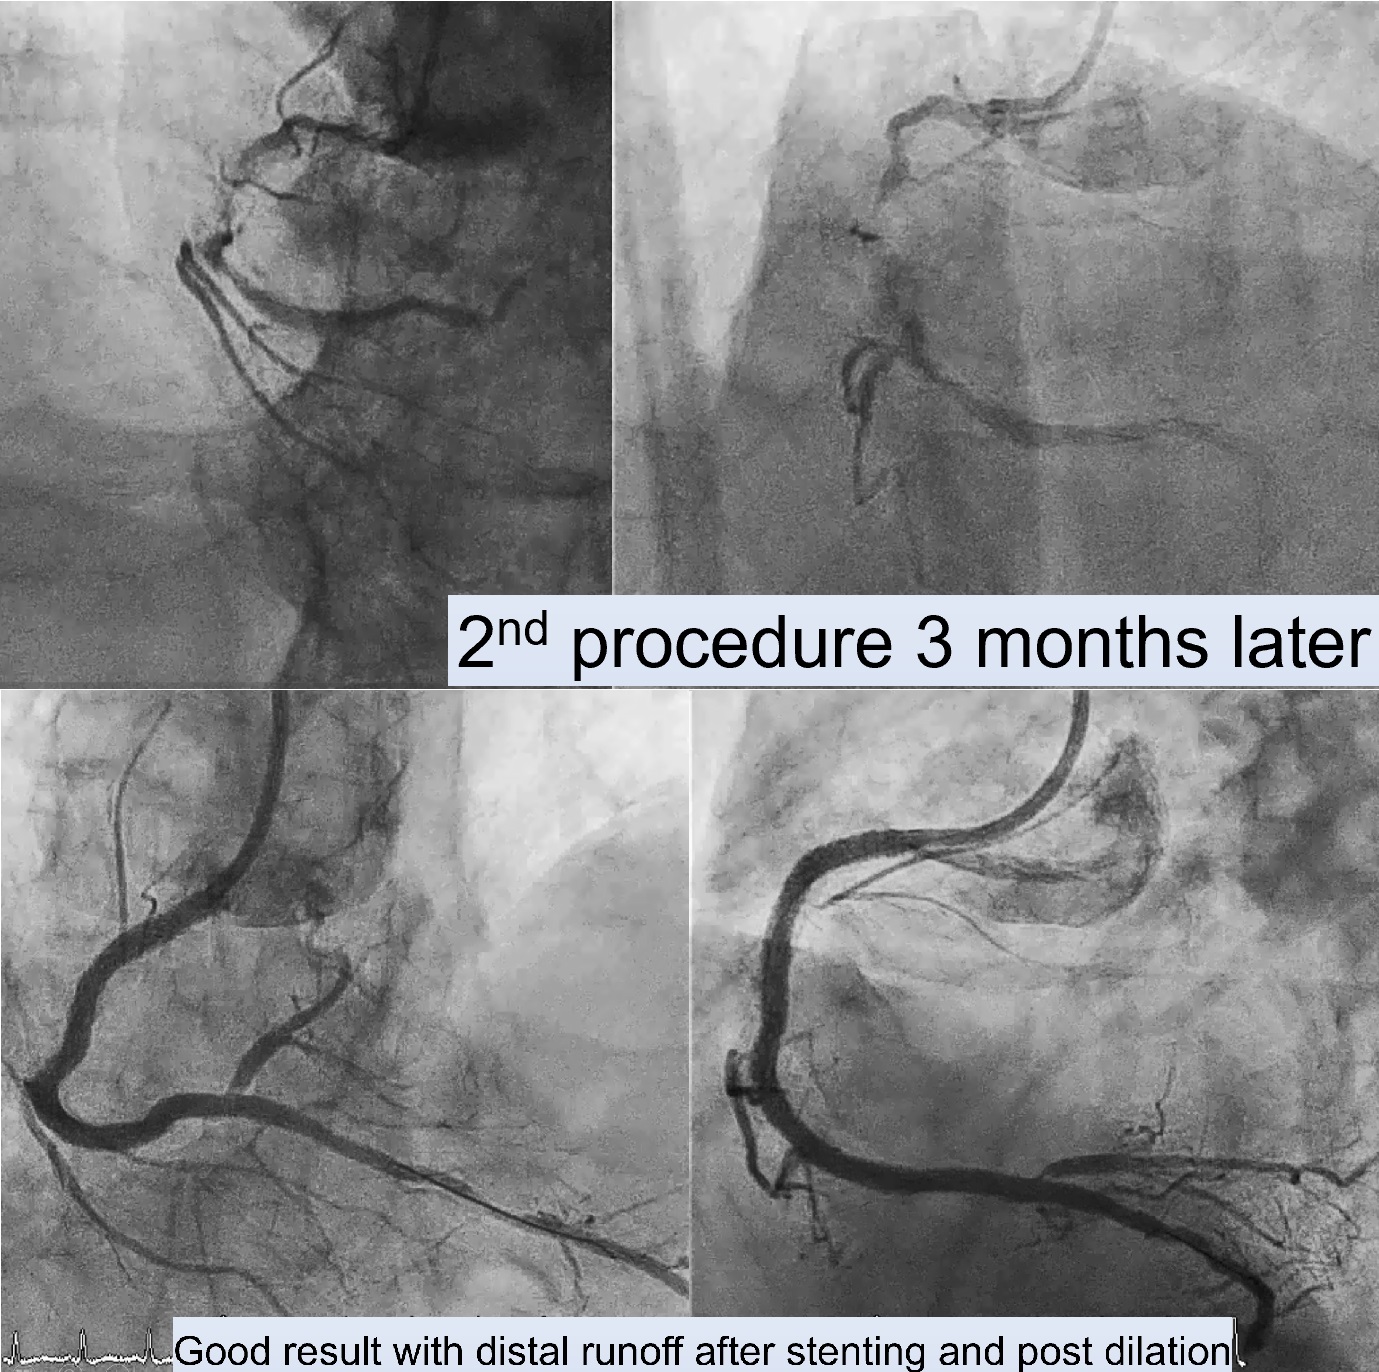

First Procedure: An antegrade approach was initially attempted with wire escalation strategies (using XTA, Fielder FC, Gaia I, II, III, Conquest pro in Cosair), but the wire entered a false lumen. Shift to parallel wire technique with Sasuke. The Gaia III wire eventually reached the distal true lumen. Balloon dilation was attempted, but the CTO segment remained undilatable. IVUS confirmed severe calcification, so a 1.25 mm rotational atherectomy (ROTA) burr was used, which led to mild improvement but still left an undilatable lesion. The procedure was paused because the patient could not tolerate lying flat for an extended time.Second Procedure was performed 3 months later. RCA still showed stenosis despite receiving collateral flow from LAD. Balloon dilation attempts were unsuccessful, necessitating a shift to a 1.75 mm ROTA burr for further plaque modification.After successful lesion modification, further preparation for stenting was performed, followed by the deployment of a 3.0 x 48 mm and a 3.5 x 48 mm drug-eluting stent (DES) in the RCA. Final IVUS confirmed adequate stent placement with good distal runoff. Additional stenting was performed in the LCx and LAD.

Case Summary

For patients who cannot tolerate prolonged procedures, particularly in complex CTO cases, a staged approach utilizing rotational atherectomy followed by drug-eluting balloon (DEB) application can be effective. The DEB provides interim drug delivery, reducing restenosis risk and allowing time for the patient to recover before the next procedure. This approach is especially beneficial for high-risk patients needing multiple sessions for complete revascularization.